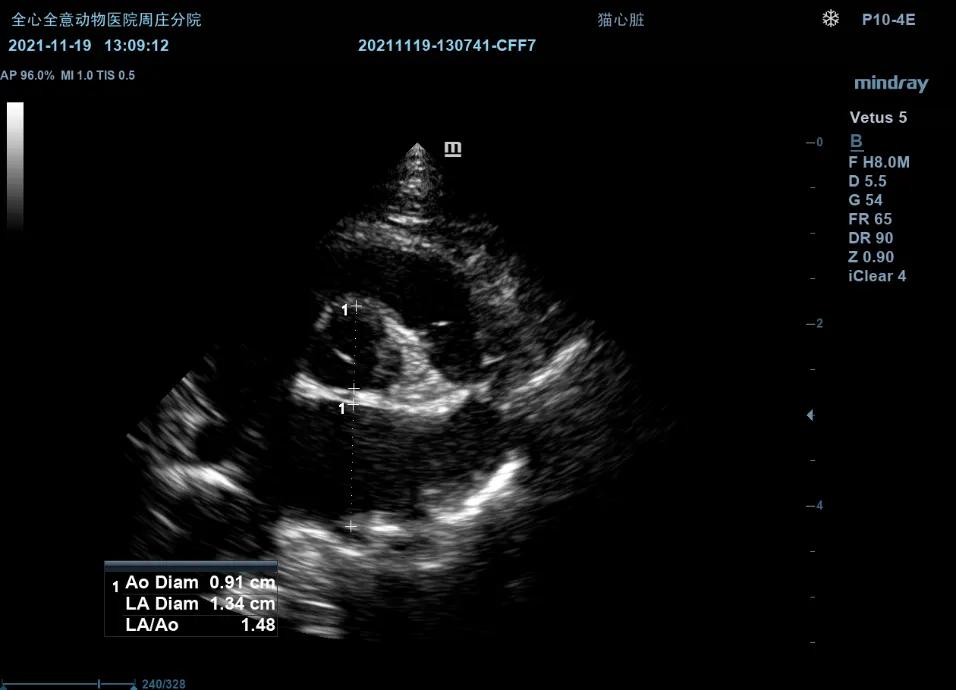

LA/AO:

右侧左室流出道观比:1.87(<2.5为正常)

右侧短轴观:1.48(<1.6为正常)